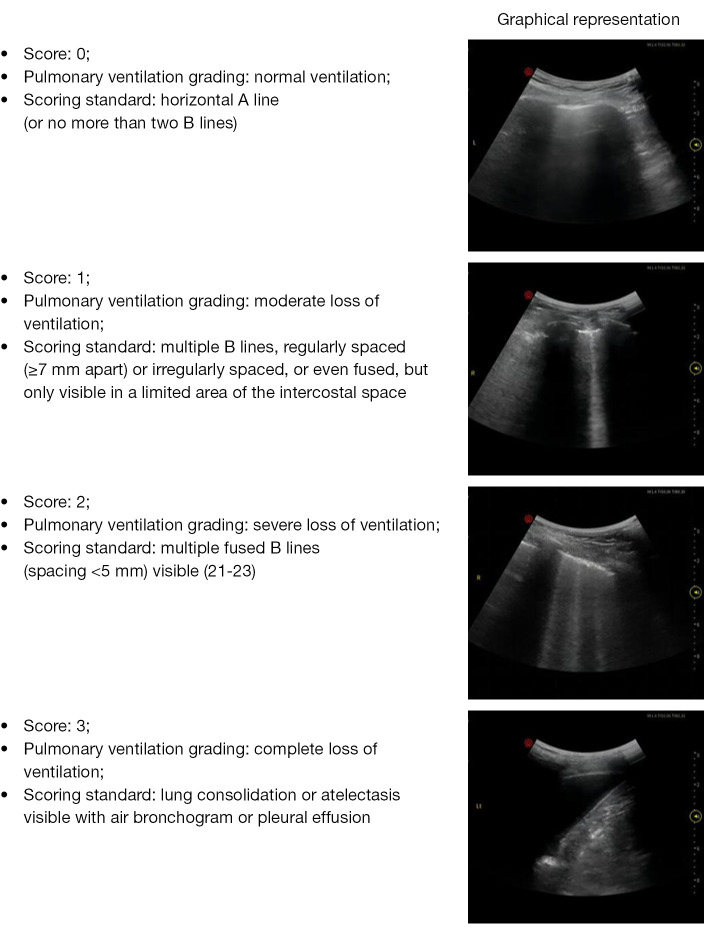

Results: Out of the 74 included patients, 23 failed weaning. There were significant differences in diaphragm excursion (DE), diaphragm thickening fraction (DTF), bilateral lung ultrasound score (LUS), total LUS, and left ventricular ejection fraction (LVEF) between the success and failure groups (P<0.05). The predictive performance of individual ultrasound parameters was as follows: LVEF achieved an AUC of 0.742 [95% confidence interval (CI): 0.642-0.842; P<0.001], with optimal thresholds of 58.05% (sensitivity: 76.5%; specificity: 69.6%); LUS achieved an AUC of 0.837 (95% CI: 0.738-0.936; P<0.001), with an 80.4% sensitivity and 82.6% specificity at a cutoff value of 17.50. DE yielded an AUC of 0.895 (95% CI: 0.821-0.969; P<0.001), with an 82.4% sensitivity and a 95.7% specificity at a cutoff value of 1.205 cm; DTF reached an AUC of 0.896 (95% CI: 0.827-0.965; P<0.001), with a 68.6% sensitivity and a 100% specificity at a cutoff value of 22.75%. A composite model integrating LVEF, LUS, DE, and DTF achieved an AUC of 0.951 (95% CI: 0.907-0.996; P<0.001), with an 88.2% sensitivity and a 95.7% specificity.